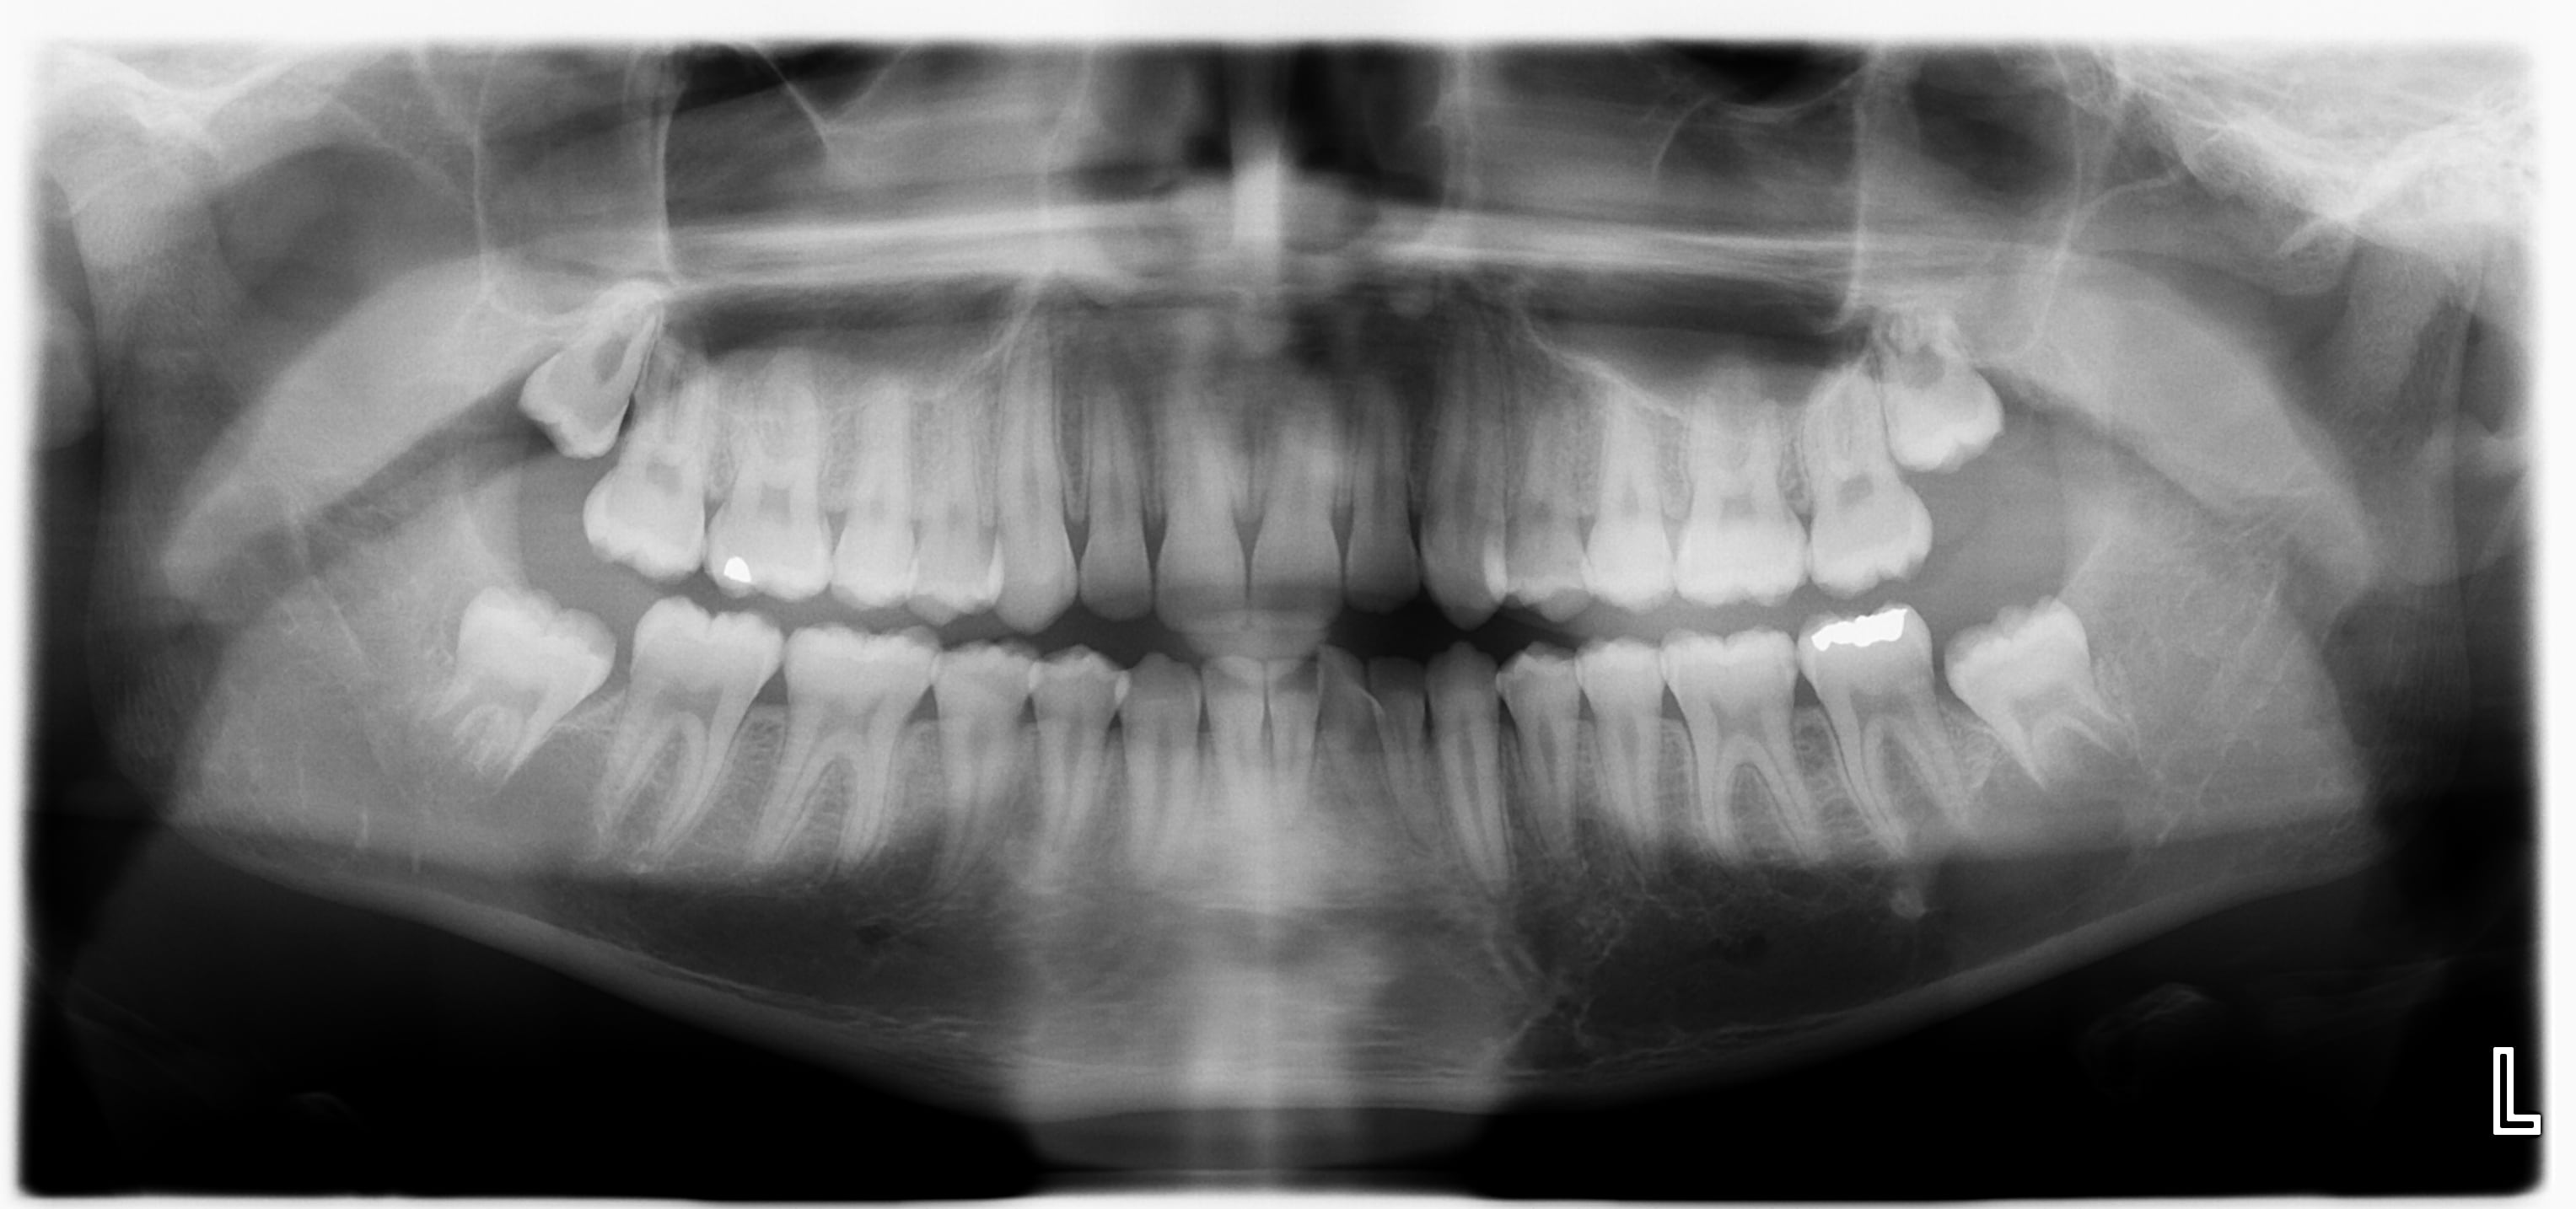

Jeune homme 15 ans, pas d'antécédents ODF, santé RAS, pano de contrôle systématique, ascendance métissée, suivi par moi depuis toujours.

C'est quoi sous la 38? On est d'accord que ce n'est pas un artefact, ça part chez le chir?

(edit: pratiquant de sports de contact)

Kyste solitaire ?

Et oui ça part chez le chir.

Conebeam pour visualiser la lésion et go pour le chir maxillo pour exérèse et anapath.

La chir a vu le grand et propose bien sûr d'enlever 38 et d'envoyer à l'anapath.

Par curiosité, et parce que je ne partage pas son avis pour le reste, qui fait quoi pour les autres dds?

Abstention, germectomie?

-le cone beam montrait bien une image radioclaire, avec une empreinte sur la corticale

-à l'extraction, kyste osseux solitaire, sans matériau à prélever pour l'anapath.